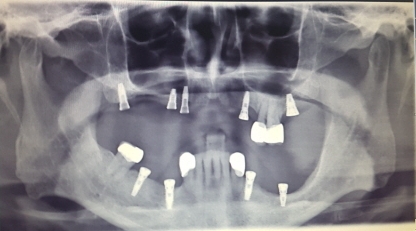

최근, 이러한 틀니의 단점을 보완할 수 있는 방법으로 무절개 임플란트(최소침습 임플란트) 시술법이 개발됐다. 잇몸을 절개하지 않는 무절개 방식의 임플란트 시술이기 때문에 출혈이나 감염 등의 위험이 없다. 시술 부위에 작은 구멍을 내 임플란트를 식립하기 때문에 기존 임플란트의 6-7 단계 과정을 3단계 정도로 줄일 수 있다. 또한, 통증이 적고 회복기간이 짧아 노인 환자들에게 적합한 시술법이다.

노인뿐만 아니라 기존 고혈압이나 당뇨, 심장질환을 앓고 있어 임플란트 시술이 불가했던 환자들에게도 무절개 임플란트를 시술할 수 있다. 이러한 전실질환자들은 과다출혈과 감염 등 합병증의 위험 때문에 임플란트 시술이 어렵지만, 무절개 임플란트 시술은 가능하다. 또한 임플란트 1개를 식립하는데 드는 시간은 약 5분으로 위험도가 낮다.

적절한 위치에 무절개로 임플란트를 식립하기 용이하며, 잘 맞지 않는 보철물에 대한 피로도가 적기 때문에 임플란트의 기대 수명 또한 늘일 수 있다. 무절개 임플란트는 이에 전신질환 환자는 물론 통증이 두려운 경우, 보다 짧은 회복기간을 원하는 경우, 시간 여유가 없어 바로 일상으로 복귀하고자 하는 경우 등 다양한 사례에 적용 가능하다.